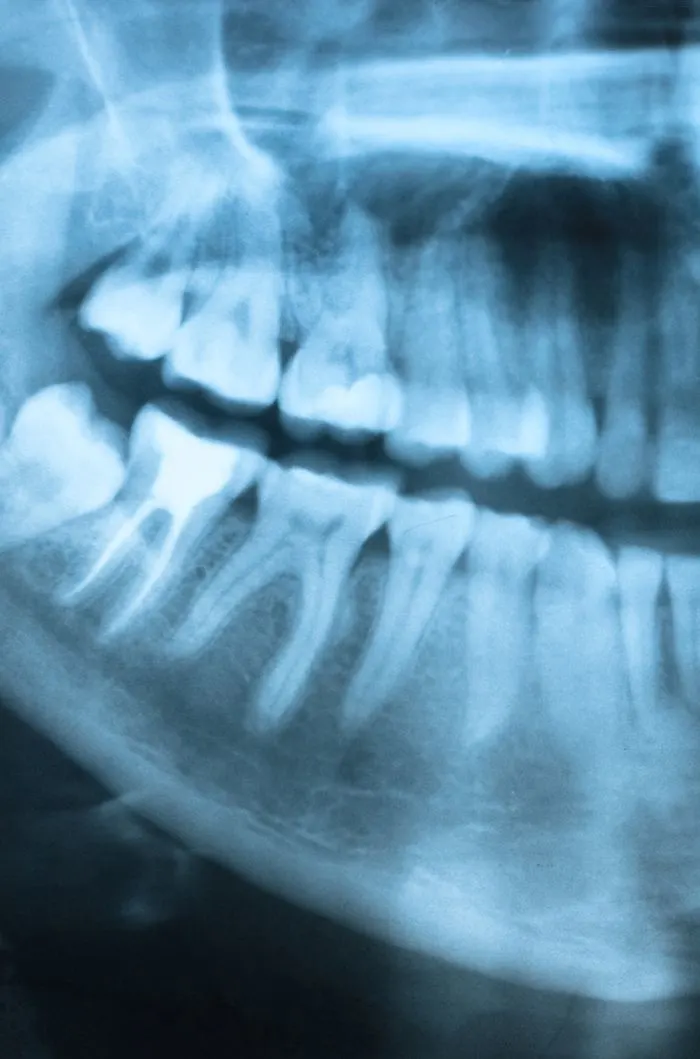

With digital x-rays, we get high-resolution images of your teeth that allow us to make more accurate diagnoses. When you’re in pain or experiencing an emergency, we can see why the tooth is reacting and if an extraction is needed.